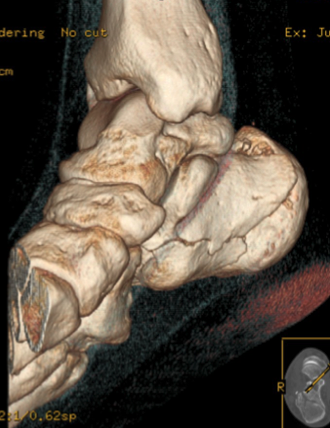

膝関節